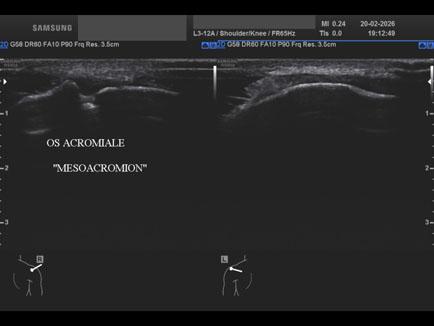

Data inserimento: 24/02/2026

Ecografia del: 20/02/2026

Strumento: Samsung

Sonda: Lineare

Età Paziente: M 20 anni

Commento all'esame: presenza di “os acromiale” (“mesoacromion”): mancata fusione di uno o più centri di ossificazione durante l’adolescenza (circa 5% della popolazione); coesiste lieve iperemia sinoviale acromion-claveare in maschio ventenne.

Conclusioni: presenza di “os acromiale” - mesoacromion (presence of “os acromiale” - mesoacromion).

Realizzazione: Dr. F. Pietro Tarini - Gubbio (PG)